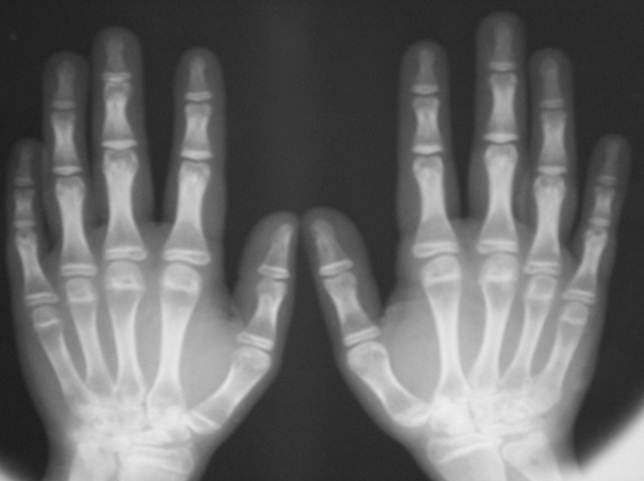

JUVENILE RH ARTHRITIS